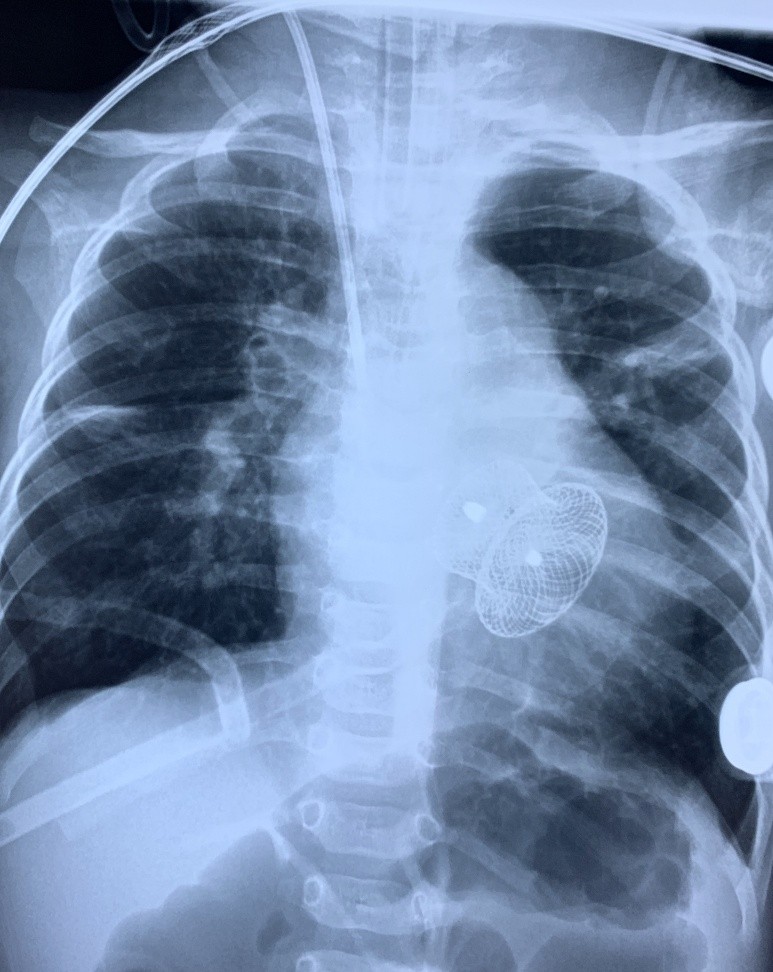

Phim chụp ngực bệnh nhi sau can thiệp (có hình dụng cụ ở giữa tim). Ảnh: BVCC

Sau khi hội chẩn, Trung tâm Tim mạch và Lồng ngực quyết định dùng kỹ thuật Hybrid để điều trị cho bệnh nhi, mặc dù rất khó khăn nhưng là giải pháp trọn vẹn nhất. Kỹ thuật Hybrid trong tim mạch là sự kết hợp cùng lúc 2 kỹ thuật cao là “phẫu thuật tim mạch” và “can thiệp tim mạch” để điều trị các bệnh phức tạp mà 1 trong 2 kỹ thuật cao này không thể giải quyết tốt được.